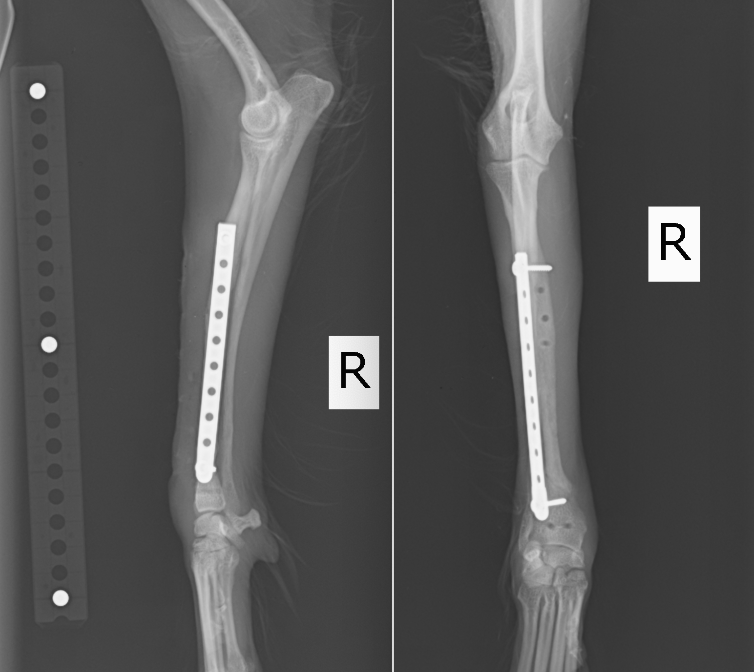

次の症例は11ヶ月のトイプードルで、スリングから飛び降りた後から足をケンケンするということで来院しました。左橈尺骨遠位斜骨折で、2日後に手術を実施しました。遠位骨折の場合尺骨(細い方の骨)には治療を行いませんが、骨折線も綺麗にあっているのがわかります。術後は次の日から足を着くことが可能で、1週間後に帰る時には通常に近い歩様で帰っていきました。その後1週間で抜糸となりますが、そこまでは散歩を5〜10分ほどにしてもらいます。ジャンプや激しい運動はしないでもらっています。その後2週間は散歩を15〜20分、その後1ヶ月は25〜30分で、その頃にプレートを1枚抜去します。

正面から見たレントゲン画像です。

横から見たレントゲン画像です。

術後のレントゲン画像です。足もまっすぐになり、尺骨という骨も綺麗にあっているのがわかります。